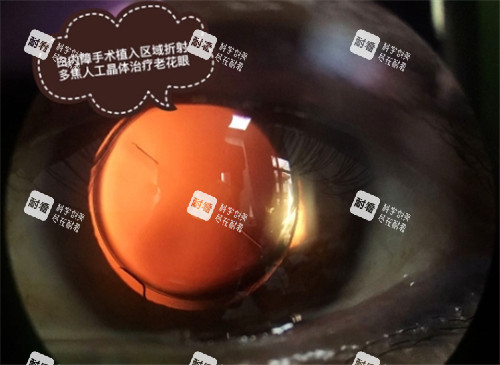

白内障手术:宋医生擅长晶状体半脱位、儿童白内障等复杂病例的手术治疗,手术技巧娴熟,经验充足。

超声乳化技术:他熟练掌握超声乳化技术,能够精密、快速地完成白内障手术,修养患者视力。

精密屈光性白内障手术:云医生擅长精密屈光性白内障手术规划设计和标准规范的临床诊疗,能够根据患者的眼部条件制定个性化的手术方案。

复杂白内障手术:对于各种复杂性白内障手术及其并发症,云医生有着丰富的处理经验,能够确保手术的安心和结果。

儿童白内障治疗:他还专注于儿童白内障的发病因素、手术时机、人工晶状体选择等方面的研究,为儿童白内障患者提供了正规的治疗。